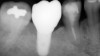

A 4.8 mm x 10 mm implant (Straumann® Bone Level Tapered [BLT], Straumann) had been placed at the mandibular first molar site and was ready for restoration. A custom healing abutment was fabricated and inserted at the time of surgical implant placement and soft tissue was sutured around the abutment using 4/0 Glycolon sutures (Osteogenics Biomedical, osteogenics.com) (Figure 13). A periapical x-ray was taken at the time of placement of the custom healing abutment to confirm full seating (Figure 14).

Fig 14. A periapical radiograph of the custom healing abutment on the implant demonstrated the development of a natural emergence profile for a mandibular molar to replicate the missing natural tooth.

Figure 14